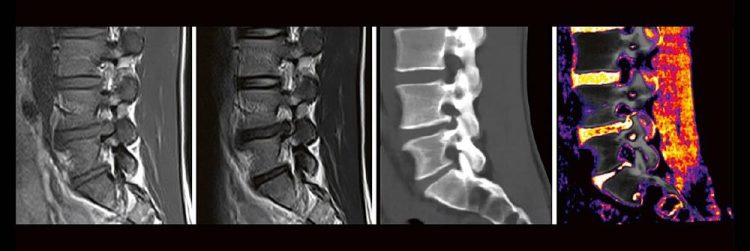

Dual-Energy CT der Wirbelsäule: Technik und klinische Praxis (Webinar | Online)

Professor Dr. med. Matthias PumbergerPD Dr. med. Torsten Diekhoff Die Dual-Energy-Computertomographie (DECT) hat für viele klinische Anwendungen bereits Einzug in die Praxis genommen. Für die Behandlung von Wirbelsäulenerkrankungen sind besonders die Darstellung von Knochenmarkveränderungen (z. B. bei osteoporotischen Frakturen) und der Bandscheibe (z. B. bei Bandscheibenvorfällen) interessant und werden intensiv beforscht. Hierdurch versprechen wir uns…Continue reading Dual-Energy CT der Wirbelsäule: Technik und klinische Praxis (Webinar | Online)